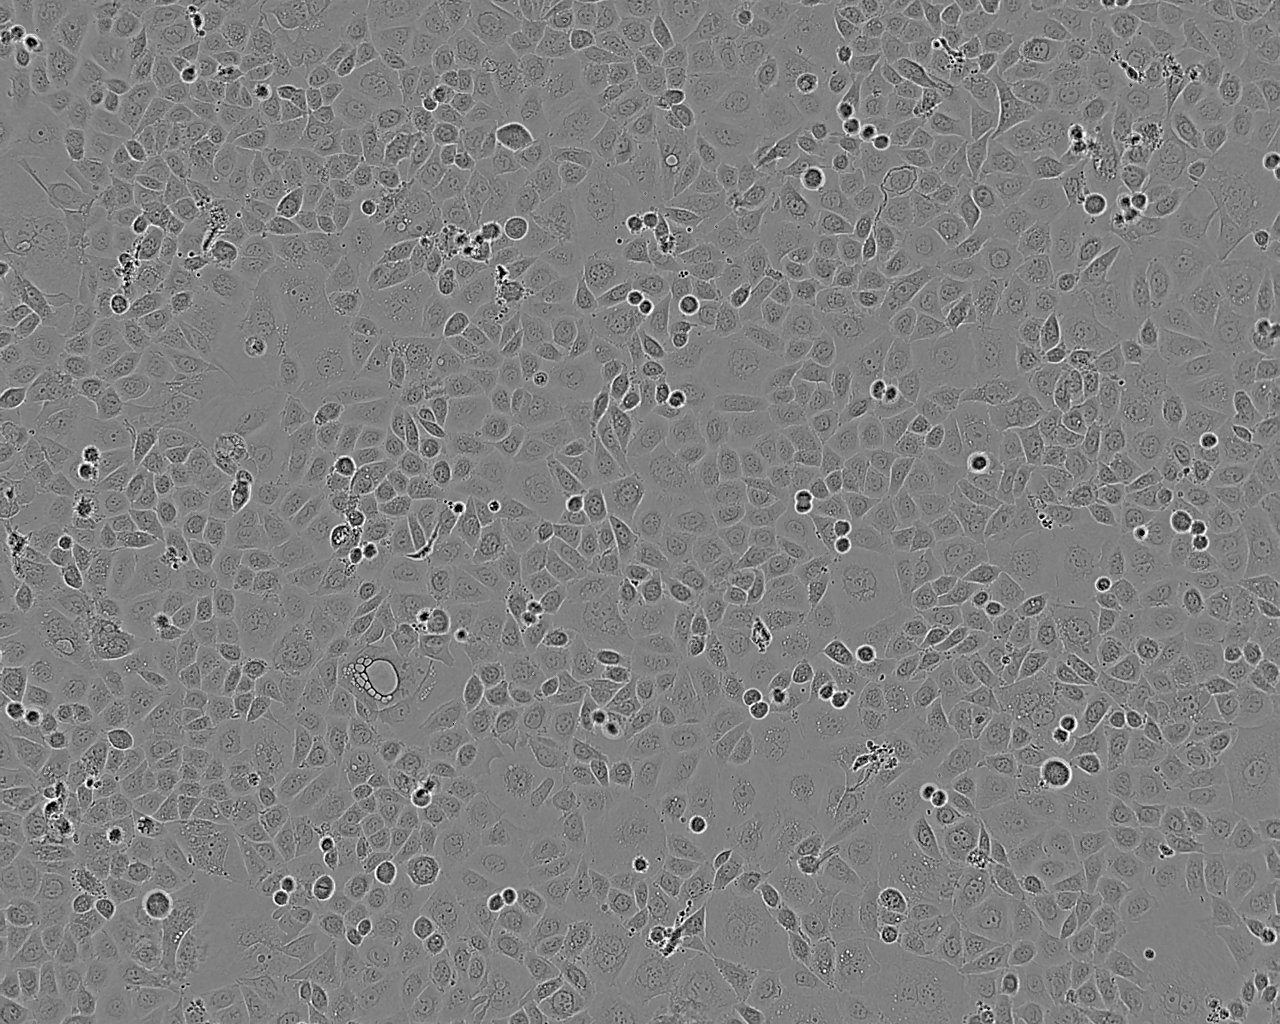

细胞形态:上皮细胞样

细胞生长:贴壁

细胞背景资料:前列腺癌;左锁骨上淋巴结转移;男性

细胞生长特性:贴壁